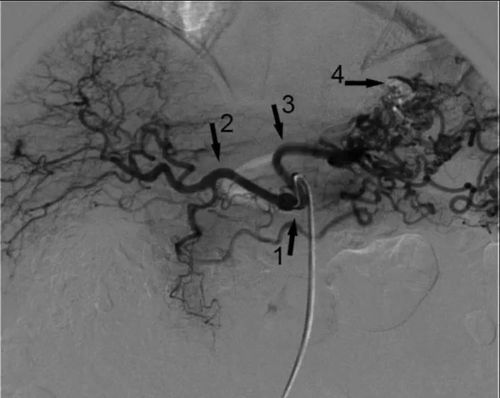

• Tiến hành chụp mạch búi tĩnh mạch dạ dày giãn qua ống thông có bóng. Đánh giá toàn bộ hệ thống búi mạch giãn và các nhánh bàng hệ, dẫn lưu.

Hình ảnh giãn tĩnh mạch dạ dày do huyết khối động mạch lách